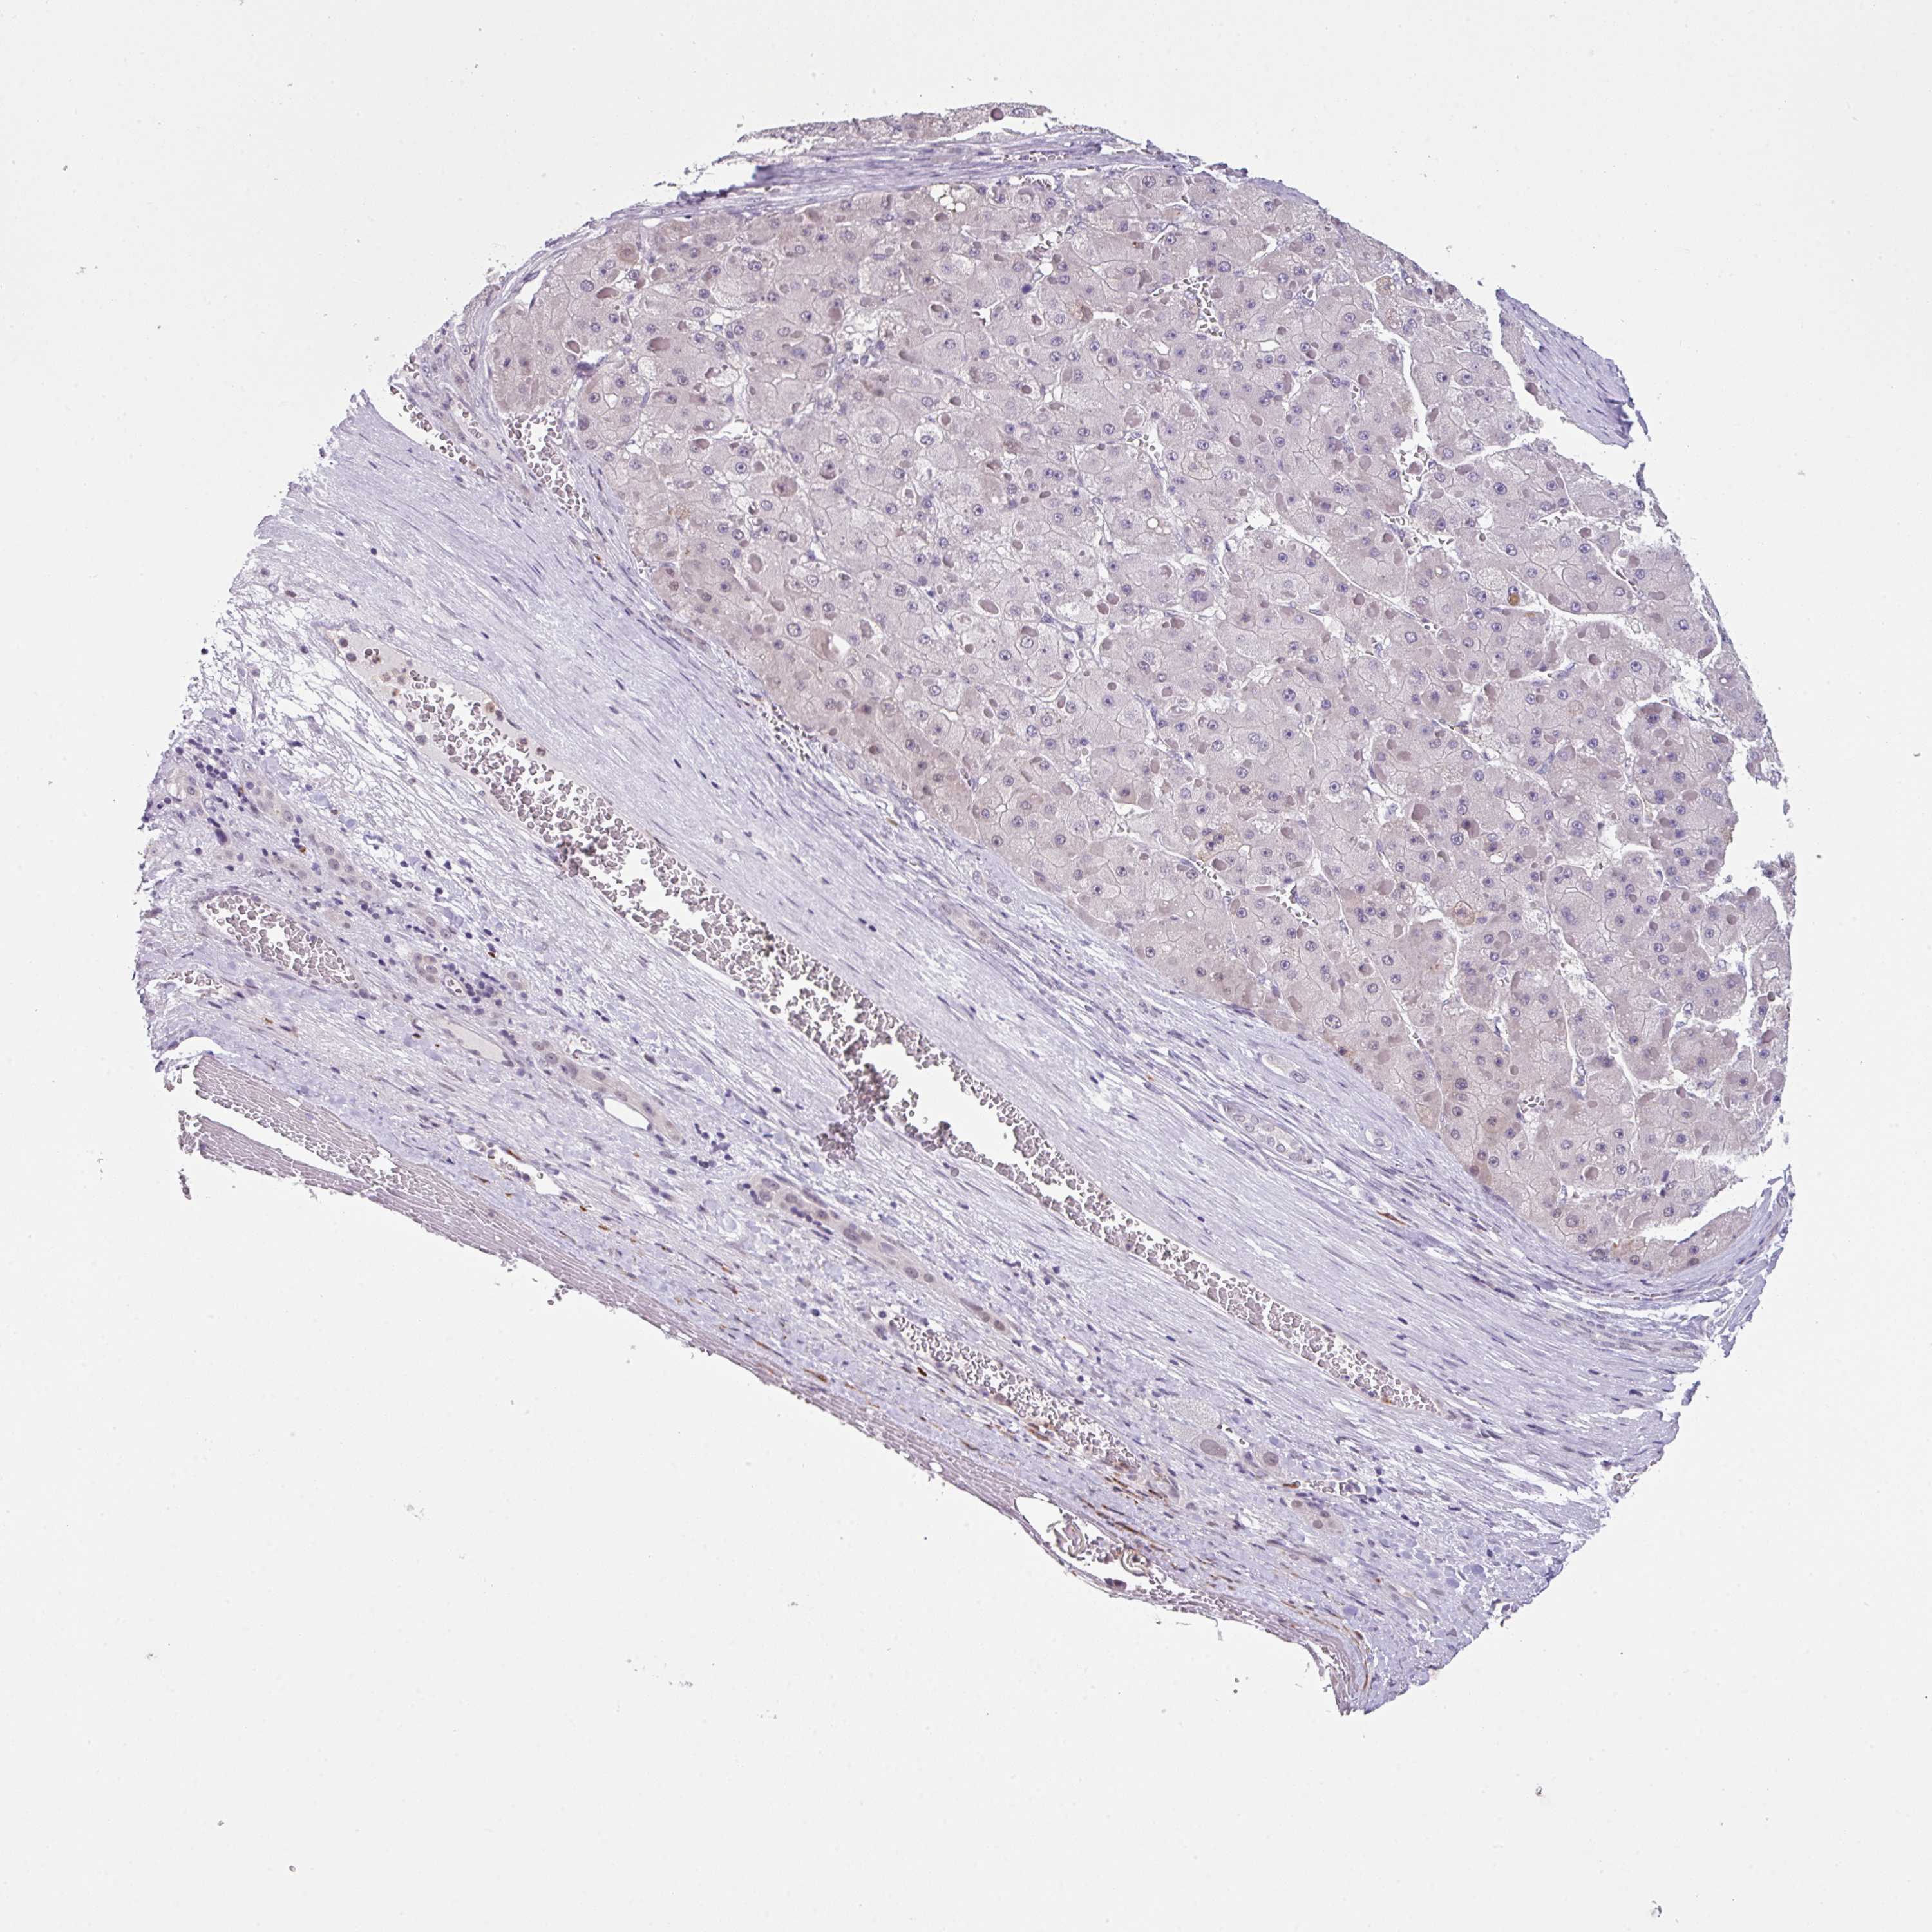

LIVER CANCER - Protein expressioni

A mouse-over function shows sample information and annotation data. Click on an image to view it in a full screen mode. Samples can be filtered based on level of antibody staining by selecting one or several of the following categories: high, medium, low and not detected. The assay and annotation is described here.

Note that samples used for immunohistochemistry by the Human Protein Atlas do not correspond to samples in the TCGA dataset.

Antibody stainingi

Antibody staining in the annotated cell types in the current human tissue is reported as not detected, low, medium, or high, based on conventional immunohistochemistry profiling in selected tissues. This score is based on the combination of the staining intensity and fraction of stained cells.

Each image is clickable and will lead to virtual microscopy that enables deeper exploration of all samples and also displays staining intensity scores, fraction scores and subcellular localization as well as patient and tissue information for each sample.

Antibody HPA053085

Staining

High

Medium

Low

Not detected

Intensity

Strong

Moderate

Weak

Negative

Quantity

>75%

75%-25%

<25%

None

Location

Nuclear

Cytoplasmic/membranous

Cytoplasmic/membranous,nuclear

Cholangiocarcinoma

Carcinoma, Hepatocellular, NOS